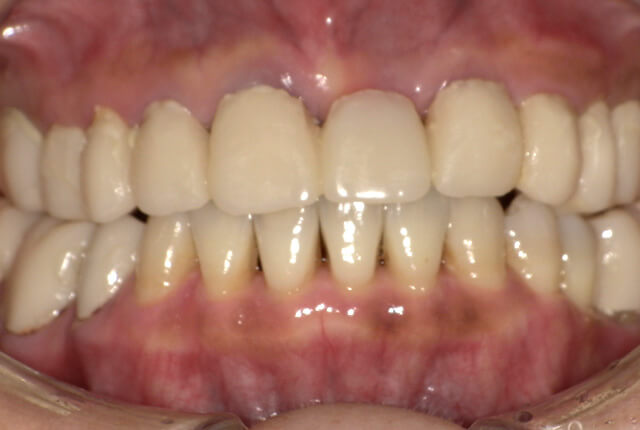

90分の治療で銀歯の状態からキレイな状態になります。噛み合わせの調整や審美面も使用しながら合わせます。

良く噛めて安心と、ご満足いただき大変嬉しく思います。笑顔も一層素敵になりました。

| 治療内容 | 欠損部インプラント 不正咬合に対し不良補綴のやり直しと合わせて咬合再構築 |

| 治療計画 | 欠損部インプラント 不良補綴のやり直しと欠損部インプラント。 咬合の再構築、なるべく歯を残せる様に治療計画を立案。 |